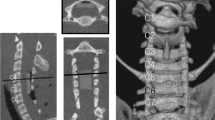

After intravenous anesthesia, the sheep were placed in the supine position, and a right longitudinal incision was made through the anterior cervical approach to the front of the cervical vertebral body. Intraoperative radiographs confirmed the C2-3 intervertebral space. The intervertebral disk was removed to the posterior edge of the vertebral body. A curette and grinding drill were used to expand the space to the size of the compression device, and the compression device was fixed at the C2-3 intervertebral space with plates and screws. The initial position of the head of the pushrod was at the posterior edge of the vertebral body (Fig. 2), and SCCMs were implanted under the skin.

Behavioral analyses were performed before and immediately after the operation and at 1, 5, 10, 20, and 30 weeks after the operation. The Tarlov scores for each sheep in the group were obtained by three observers who were blinded to the group designations and then averaged for the groups [3, 17]. Cervical X-ray and computed tomography (CT) examinations were performed before and immediately after surgery.

Cervical CT scans were also performed at 1, 5, 10, 15, 20, and 30 weeks after the operation, and the encroachment ratio (ER) of intraspinal invasion was calculated (Fig. 3). Encroachment ratio was defined by ER = (1-MD/CD)100%, where MD is the minimal distance between the screw and the posterior canal wall and CD is canal diameter, both at the level of compression.

Imaging observation

The ER in Group B was 33.0 ± 1.8% at 10 weeks and 64.8 ± 1.9% and 66.3 ± 3.2% in Groups C and D, respectively, at 20 weeks (Table 1). The Pearson correlation coefficient between ER and time in Groups B, C, and D was r = 0.993 (p < 0.001); the linear regression equation between ER and time (t) during the pushing period was ER (%) = 3.26 × t (Fig. 4). ER was negatively correlated with the Tarlov score (Pearson correlation coefficient r = -0.878, p < 0.001). However, the data in Group D at 30 weeks did not follow the correlation, with low ER and Tarlov scores.